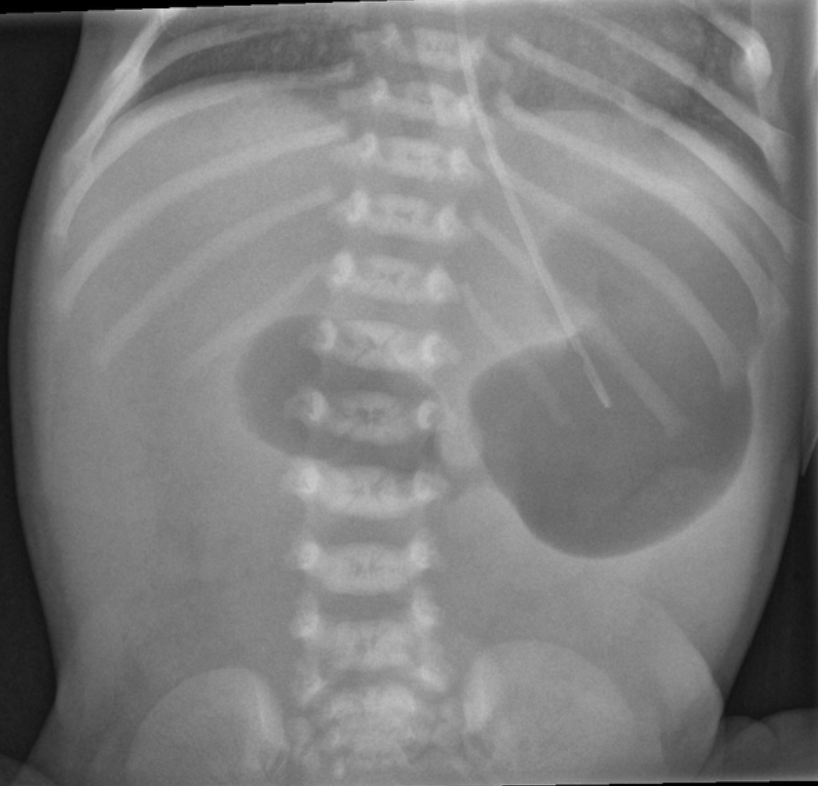

10 day old vomiting, abdominal distension, stooling blood, ER team will institute this treatment plan

What is make the baby NPO, resuscitation with fluids, pressors, intubation if needed, IV abx, Surgical consult, admission